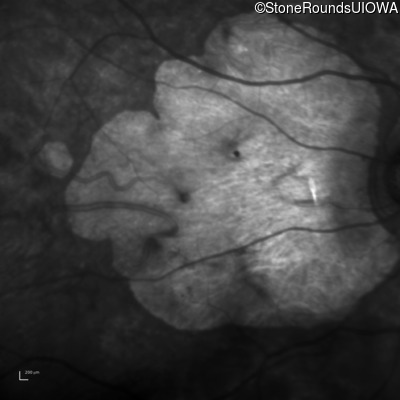

Infrared Fundus Photograph - Right - 20/300

Exemplar